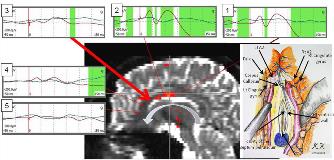

Rationale: Recent neuroimaging studies suggest that intractable epilepsy involves pathological functional networks as well as strong epileptogenic foci. Combined cortico-cortical evoked potential (CCEP) recording and tractography is a useful strategy for mapping functional connectivity in normal and pathological networks. In this report, we demonstrate the efficacy of preoperative combined CCEP, high gamma activity (HGA) mapping, and tractography for surgical planning and of intraoperative CCEP measures for confirmation of selective pathological network disconnection.  Methods: We treated four intractable epilepsy cases, all with subdural grid implantation, using presurgical CCEP, HGA, and diffusion tensor imaging (DTI)-based tractography analysis as well as continuous CCEP monitoring during resection surgery.  Results: All four patients in this report had measurable pathological CCEPs. The mean N1 latency of normal CCEPs related to language functions was 22.2 ± 3.5(mean ± SD) ms, whereas pathological CCEP latencies varied between 18.1 and 22.4 ms. Pathological CCEPs diminished after complete disconnection in all cases. All of them were in long-term postoperative seizure-free status, although one has still suffered from visual aura every other month.  Conclusions: Combined CCEP measurement, HGA mapping, and tractography greatly facilitated targeted disconnection of pathological networks. Although CCEP recording requires technical expertise, it allows for assessment of pathological network involvement in intractable epilepsy and may improve seizure outcome.  Funding: N/A